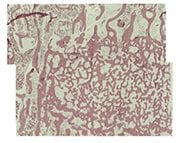

genex Implantation

6 Weeks

8 Weeks

(Large animal model. Decalcified histology H&E stain)

genex restores bone to normal trabecular structure in 36 weeks1